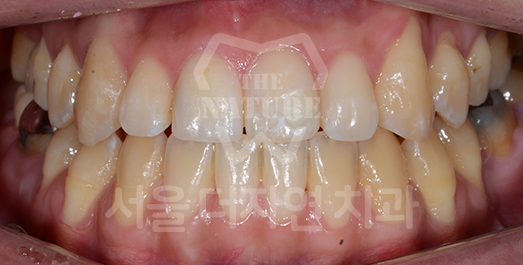

Impacted Tooth Solution

An impacted tooth remaining within the alveolar bone can cause damage to adjacent teeth.

Orthodontic traction is used to guide the impacted tooth into its correct position,

allowing it to erupt and seat normally within the dental arch.

-

AFTER: 2013.07.08

Side effects such as root resorption and gingival recession may occur.